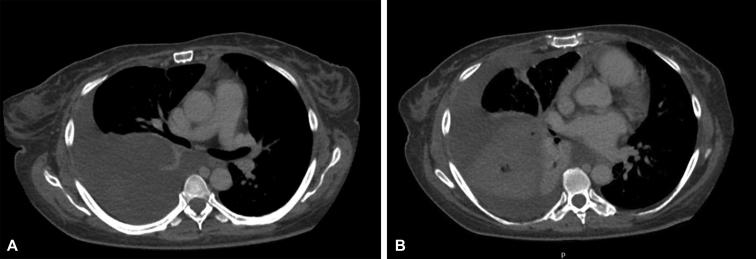

Minimally invasive lobar preservation in the setting of spontaneous middle-lobe torsion.

JTCVS Tech. 2023 Nov 23;23:154-157. doi: 10.1016/j.xjtc.2023.11.009. eCollection 2024 Feb.